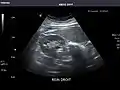

Right kidney